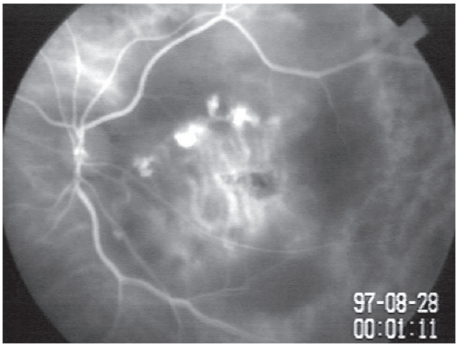

2013年团队收治了一例单眼黄斑区脉络膜新生血管的老年患者,其辗转国内各大医院且眼内多次抗血管内皮生长因子治疗效果差。经过详细的眼底检查,笔者团队关注到该患者ICGA检查中脉络膜新生血管病灶周围有不寻常的弱荧光病灶,弱荧光病灶的轮廓细碎具有特征性。通过文献检索,团队认定该患者诊断是持续性鳞状黄斑病变(persistent placoid maculopathy, PPM)继发脉络膜新生血管。PPM是罕见眼底疾病,以往仅在白人中有个位数病例报道,亚洲尚无病例报道。同时团队注意到PPM的病灶定位不清,多年来发表的研究莫衷一是。认识到该特殊眼底病例后,团队长期积累类似表现的病例,在不断分析验证中发现PPM病灶一致的准确定位。2024年经过10年的病例积累,团队首次报道了亚洲人群的16例PPM病例系列,同时是国际上最大的PPM病例系列[14]。揭示了PPM病变所在的真正层次以及迁徙进展的特性,完善了分型和描述术语,为国际上关于病变层次的争论提供翔实的影像学依据。

此前,由于病例罕见,PPM的主要受累层次众说纷纭。团队借助最大的病例系列分析和高分辨率OCT,首次观察到PPM的地衣样ICGA弱荧光病灶对应于RPE-Bruch膜复合体的增厚或裂隙状、丘状的RPE与Bruch膜层间病灶(图7),为国际上关于PPM病变所在真正层次的争论提供新的确实影像学依据。同时鉴于PPM病灶特征,团队建议使用“地衣样(lichenoid)”来代替“鳞状(placoid)”来准确描述PPM在 ICGA 上弱荧光的独特轮廓和 PPM病灶在RPE下的扁平生长模式。病变在 RPE 和 Bruch膜之间的潜在空间中迁徙和延伸可能是地衣样外观和进展模式的原因。

图 7 PPM的ICGA弱荧光对应于 OCT 上的RPE下病灶

Figure 7 ICGA hypofluorescence of PPM corresponds to sub-RPE lesions on OCT

( A、B、C)PPM 病变在 ICGA 上表现为地衣样弱荧光,分为融合状(B)和簇状(A、C),其中一个病例的病灶位于后极部以外(C);(D、E、F)它们对应于 OCT 上 RPE-Bruch 膜复合体的增厚(D 中的黄色箭头和黄色框内范围,与蓝色框内范围中正常的 RPE-Bruch膜复合体相比)和RPE下中等反射的裂隙状(E 中的黄色箭头和黄色框内范围)或丘状(F 中的黄色箭头)病灶。 红色箭头,指向 RPE 和 Bruch膜之间。弱荧光的强度与RPE下病灶的厚度相关(C、F),较暗的弱荧光与较厚的RPE 下病灶相关(箭头 1 和 2 之间的区域,与箭头 2 和 3 之间的区域相比)。OCTA在PPM病灶处的RPE下未发现异常血流信号,但在相应的en face OCT 上显示低反射的病灶形态(绿色框内范围)。

(A, B, C) PPM lesions appear as lichen-like hypofluorescence on ICGA, categorized as fused (B) or clustered (A, C), with one case showing lesions outside the posterior pole (C). (D, E, F) These correspond to thickening of the RPE-Bruch's membrane complex on OCT (yellow arrows and inset in D, compared to the normal RPE-Bruch's membrane complex in the blue inset) and sub-RPE medium-reflective slit-like (yellow arrows and inset in E) or mound-like (yellow arrows in F) lesions. Red arrows point to the space between the RPE and Bruch's membrane. The intensity of hypofluorescence correlates with the thickness of sub-RPE lesions (C, F), with deeper hypofluorescence associated with thicker subRPE lesions (area between arrows 1 and 2 compared to the area between arrows 2 and 3). OCTA shows no abnormal blood flow signals at the sub-RPE level in PPM lesions, but en face OCT reveals hyporeflective lesion morphology (green inset).

根据病灶在ICGA晚期弱荧光的形态和进展模式,PPM的地衣样病灶可分为两型:融合状和簇状。本组PPM患者脉络膜新生血管的发生率为48%,融合状患者因病变具有基底,继发脉络膜新生血管更常见。

几种类型的脉络膜炎需要与 PPM 相鉴别,包括黄斑型匍行性脉络膜炎、急性后极部多灶鳞状色素上皮病变和急性梅毒性后极部鳞状脉络膜视网膜炎。三者与 PPM 具有一些类似的眼底血管造影特征;然而,PPM具有独特的地衣样外观。此外,OCT显示这些疾病的受影响层次不同。PPM是唯一位于RPE下间隙的病变,而匍行性脉络膜炎、急性后极部多灶鳞状色素上皮病变的病灶位于脉络膜,继发累及光感受器层和RPE层,急性梅毒性后极部鳞状脉络膜视网膜炎的病灶直接累及光感受器层和RPE层。另外ASHS-LIA征象、单侧RPE发育不良等病灶在形态上与PPM有相似处,需要鉴别诊断。